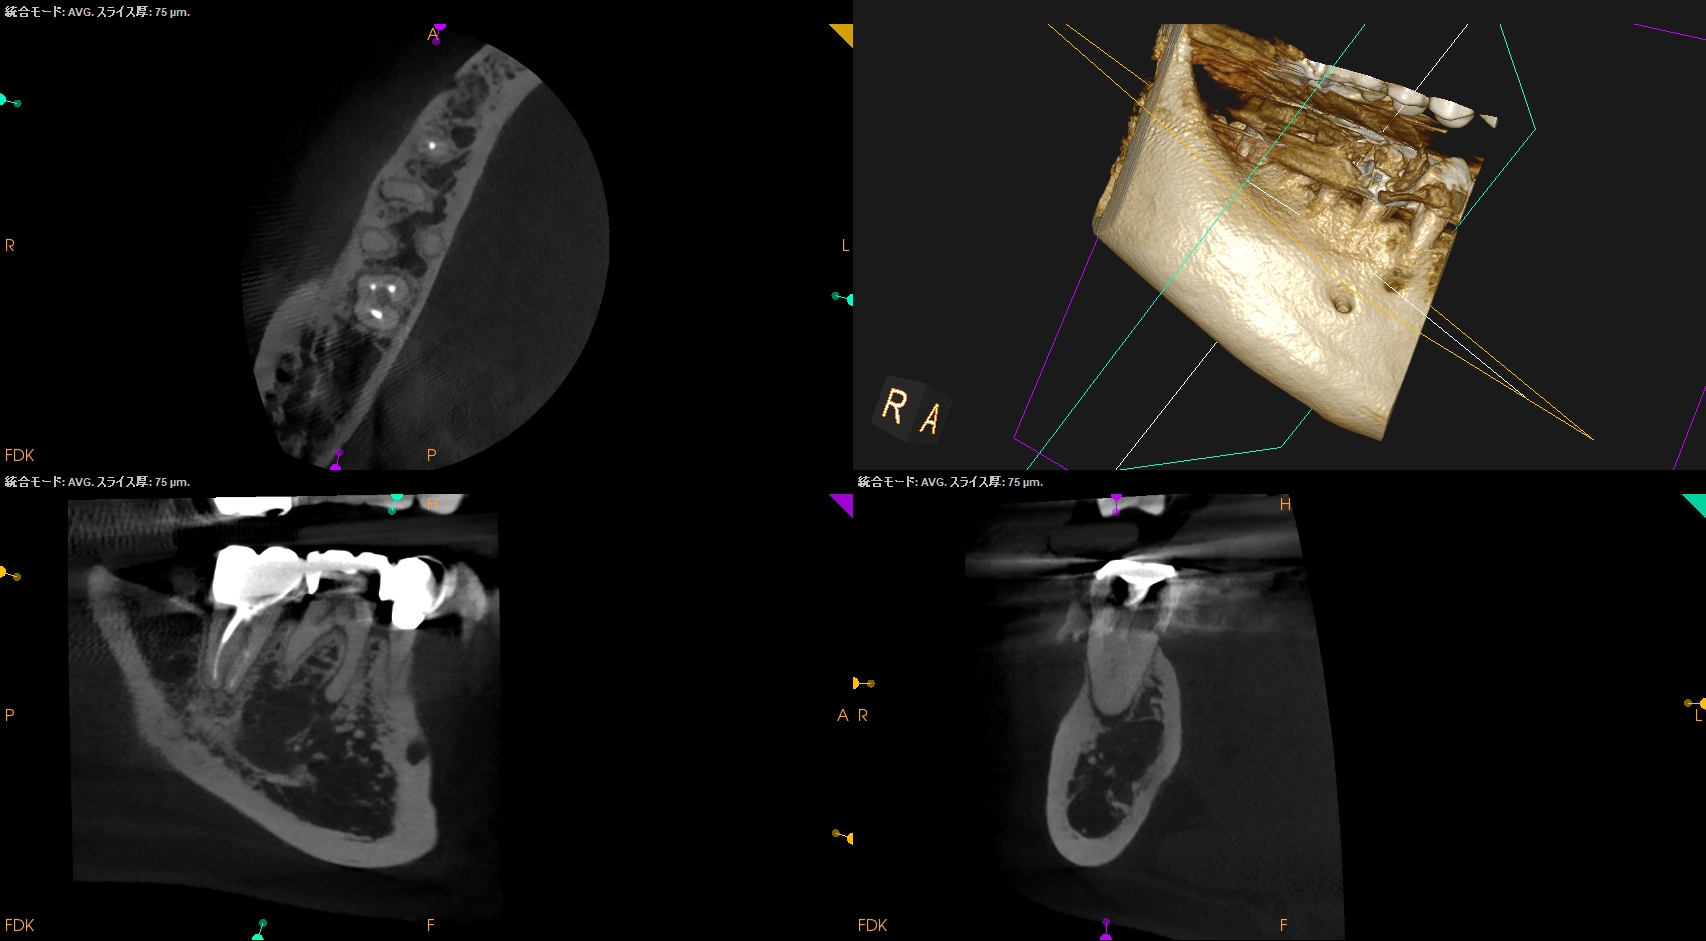

湾曲根管の形成方法は種々あるが、ColtenのHyFlex EDMの説明書には以下のようにある。

#10.05でグライドパスをしてその後に#20.05から始めるというものだ。

が、このHand FileがC+ Fileであれば#10.05を使用しなくても良くなるという話は講演会やセミナー等で私がよくする話だが、今回は

RadixはC Fileの#8で穿通している。

C Fileのテーパーは2なので0.5mm上部は#9である。

が、石灰化が極めて強くC Fileの#8をApexからさらに押し出す(突き出す)ことができなかった。

#6を使用したがこれもキツくApexから突き出せなかった。

このような場合(テーパー2度の#6,8が根尖から出せないくらい石灰化した根管の根管形成を行う場合)は、

HyFlex EDM #10.05を使用しなければならない。

今日はそれについて解説してみよう。

#10.05を2回通し、

#20.05を3回通し、

#25.Vも3回通し、

#40.04は1回だけ通している。

ちなみに形成中に私が見ている絵はファイルが根管に入り形成されている様(動き)ではない。

私が見ているのはこの絵の矢印部分である。

#10.05

#20.05

#25.V

#40.04

形成前に根管にファイルを入れてラバーストッパーからReference Pointまでの距離が形成できる根管の距離であるということがわかる。

この距離は、形成の都度、短くなり形成量は減少していく。

これを無理に押し込めるとレッジができる。

Freedmanが言う通りだ。